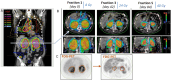

Current treatment paradigms for oligometastatic non-small cell lung cancer (NSCLC) utilize systemic chemotherapy alone or in combination with immune checkpoint inhibitors (ICIs). The addition of ICIs in NSCLC has led to significant improvements in survival; however, recurrence remains common. New methods are needed to enhance anti-tumor immune responses and improve patient outcomes. Here, we present the first case of utilization of the Ethos OART platform to deliver multi-site pulsed hypofractionated radiotherapy in a patient with oligometastatic disease on the single arm prospective clinical trial SiCARIO (Split-Course Adaptive Radioimmunotherapy in Oligometastatic NSCLC, NCT05501665). A 67-year-old man with stage IV NSCLC with metastases to bilateral adrenal glands, retroperitoneum, and mesentery was prescribed treatment of 40 Gy in 5 fractions on SiCARIO in combination with SOC chemoimmunotherapy. A multi-target single isocenter approach was utilized to treat nine distinct targets in five total isocenters. Treatment plans were generated using an isotopic approach prioritizing organ at risk (OAR) constraints with the goal of minimum coverage of at least 30 Gy in 5 fractions. CBCT was acquired with each fraction to generate new targets and OAR contours based on anatomic changes with the patient on the treatment table. A comparison of an adapted plan to a base plan was performed online with a selection of superior plans based on target coverage and OAR constraints. The adapted plan was deemed superior for all but 1 fraction of a single isocenter for this patient. The discussion will focus primarily on the bilateral adrenal isocenter, where bulk tumor shrinkage of greater than 80% was observed in this patient with corresponding significant dosimetric benefits. This case demonstrates a potential clinical benefit of OART in multi-metastasis RT. Further data is needed to confirm the safety and efficacy of this approach. Enrollment is ongoing.